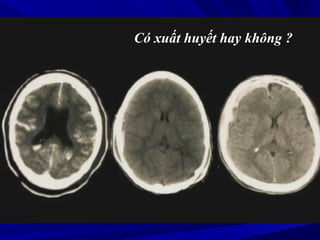

Có xuất huyết hay không ?

Xuất huyết màng não Máu tụ ngoài màng

cứng

Máu tụ dưới màng

Phân biệt xuất huyết và vôi hóaPhân biệt xuất huyết và vôi hóa

Vôi hóa đối xứng, không có hiện tượng phùVôi hóa đối xứng, không có hiện tượng phù

não và không có hiệu ứng choán chnão và không có hiệu ứng choán chỗỗ

Xuất huyết không đối xứng, có phù não chungXuất huyết không đối xứng, có phù não chung

quanh và có hiệu ứng choán chổquanh và có hiệu ứng choán chổ

Ðo mức độ cản quangÐo mức độ cản quang

Vôi hóa > 120 HuVôi hóa > 120 Hu

Xuất huyết = 40-90 HuXuất huyết = 40-90 Hu